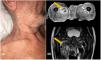

We report the case of two patients with erythroderma and hip abscess. Patient 1 was a 70-year-old woman who presented persistent psoriatic erythroderma despite treatment with etretinate, methotrexate, and cyclosporine (Fig. 1A). She was admitted to the hospital in March 2021 with a Psoriasis Area and Severity Index (PASI) of 41, and a body surface area (BSA) of 58. The psoriatic plaques were highly inflammatory with broken pustules on their surface, but without clear foci of erosions. One month later, she reported left thigh pain. No abnormalities were detected by X-ray and ultrasonography. Within one week, she developed chills and a fever. Blood cultures were positive for methicillin-sensitive SA (MSSA). With the suspicion of an infectious complication in the hip, MRI was requested, revealing a pus collection into the iliac muscle.

Patient 2 was a 76-year-old man who had a 2-year history of eczema outbreaks. He was admitted to the hospital after developing erythroderma with lymphadenopathy (Fig. 1B). A skin biopsy confirmed the clinical suspicion of mycosis fungoides. The complementary tests did not show clonality in peripheral blood or lymph nodes, so the diagnosis of mycosis fungoides stage IIIa (T4N1aM0B0) was established. Over the following days, the patient developed malaise, fever, and hip pain. Blood cultures were positive for MSSA and Streptococcus pyogenes. Body CT showed an iliac abscess. Endocarditis was discarded as the patient had a mechanical heart valve (Fig. 2).